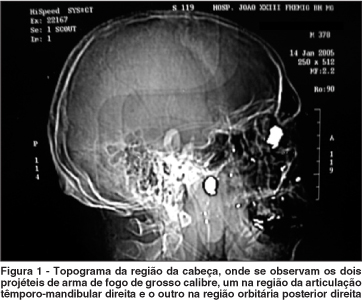

Constatou-se dois trajetos de projétil de arma de fogo de grosso calibre, ambos extra-cranianos (Figura 1). O primeiro entrou pelo nariz e se alojou na articulação têmporo-mandibular direita, causando uma paralisia facial periférica ipsilateral. O segundo projétil entrou pela nuca, margeando a coluna vertebral, sem no entanto atingí-la; fraturou o osso maxilar direito e assoalho orbitário, alojando-se na região intra-orbitária posterior direita, dentro do cone muscular.

No caso em questão, esta força propulsora foi gerada pelo projétil de arma de fogo que, ao adentrar a região orbitária posterior, projetou o globo ocular para frente, rompendo, desta forma, as fibras nervosas do nervo óptico, junto à sua inserção posterior (Figuras 1 a 6).